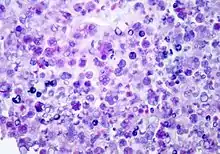

P. wickerhamii has a round to elliptical cell shape measuring 3–11 µm in diameter. The organism has thick wall (theca) with internal septations that form the small wedge-shaped endospores, which are arranged radially and moulded (morula-like form).[1] Reproduction is asexual by release of the spores from the sporangia, which can occur every 5–6 hours in ideal conditions.[2]

Diagnosis can be made through culture of diseased tissue in Sabouraud dextrose agar or by visualization of sporangia containing sporangiospores on tissue biopsy (using hematoxylin/eosin, GMS, or PAS histochemical stains). The organism incites a chronic granulomatous inflammation with infiltrate of histiocytes, lymphocytes, giant cells and occasional eosinophils.